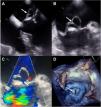

Varón de 67 años con síndrome constitucional, fiebre, disnea y soplo sistodiastólico aórtico. El ecocardiograma mostró vegetación aórtica y un gran seudoaneurisma del velo anterior mitral (fig. 1flechas), sin afectación valvular ni perianular, con hemocultivos positivos para Streptococcus salivaris. Con diagnóstico de endocarditis aguda se realizó sustitución mitroaórtica bajo circulación extracorpórea. La atriotomía izquierda mostró pseudoaneurisma gigante (figs. 2A y B) violáceo de todo el velo anterior mitral sero-saguinoliento (figs. 2C y D). El postoperatorio cursó sin incidencias con cultivos valvulares negativos. La asociación entre el seudoaneurisma postendocardítico aislado del velo anterior mitral, sin afectación valvular o de la continuidad mitroaórtica es infrecuente. El ecocardiograma es clave en elegir el tratamiento y el momento quirúrgico.